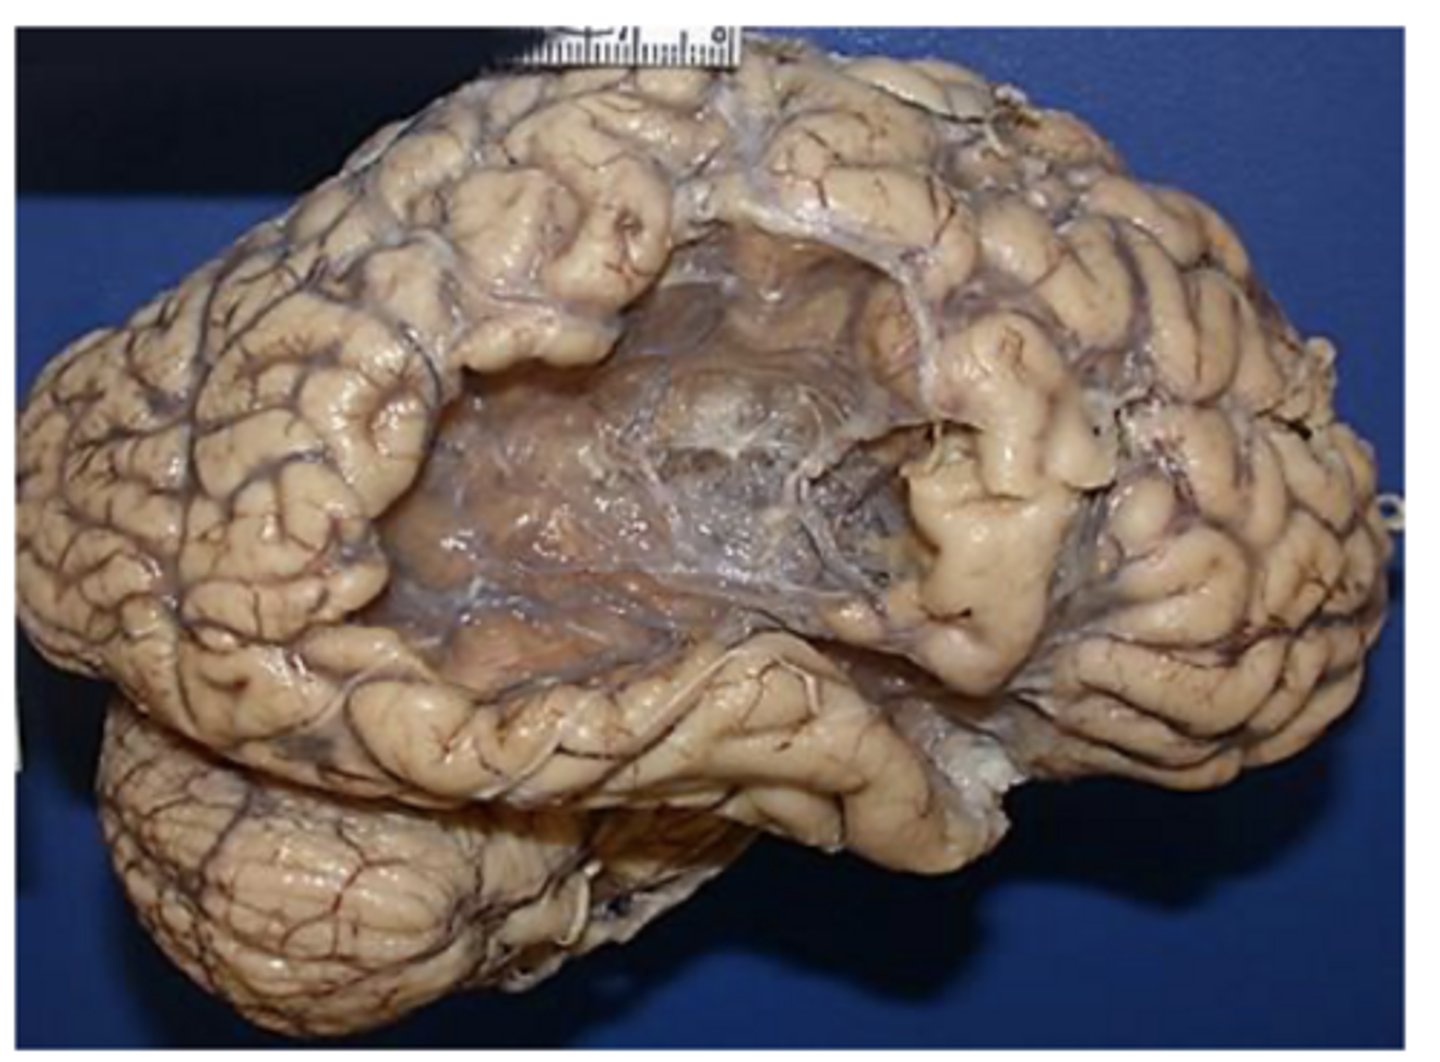

smaller lacunar infarct

old MCA infarct -> not the cause of death, but can see the changes/damage post-mortem from a previously experienced MCA infarct

-cystic cavity

What does the histopathology of an ischemic stroke (infarct) reveal at 2-3 weeks or months after the stroke?

2-3 weeks or months after the stroke:

-gliosis